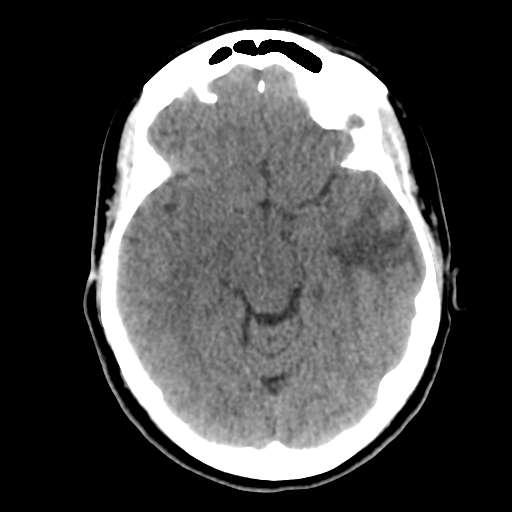

Bệnh bạch cầu biểu hiện ở hệ thần kinh trung ương (Leukemia)